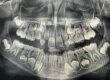

- Mellkas röntgen lelet. Ha rendelkezik ilyen lelettel, akkor az is megfelel, de 1 évnél nem lehet régebbi.